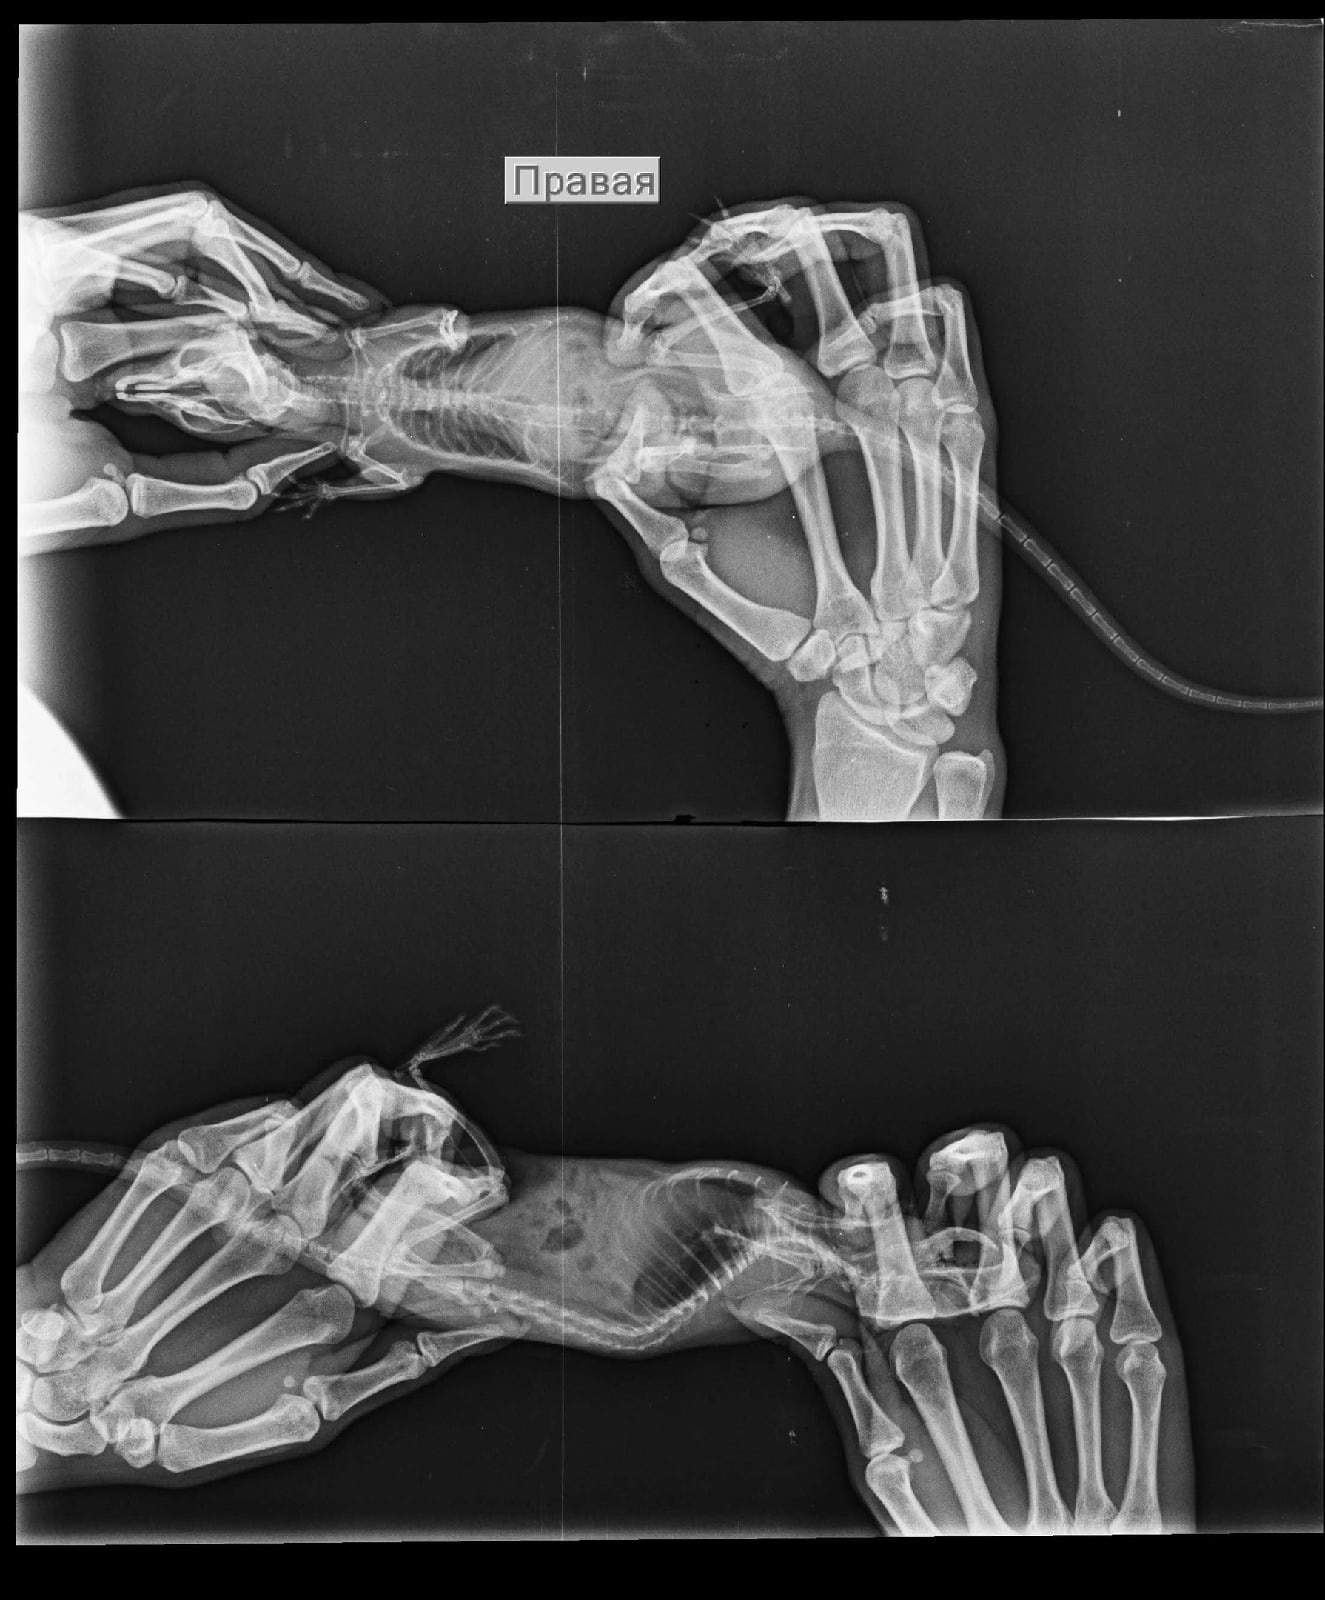

Добрый вечер, дополним историю лечения: лечились небулайзером беродуал 1мл + 4мл физраствор и ципрофлоксацин 50/50 с физраствором. Довольно долгое время. Ещё прикрепляем старые рентгены.